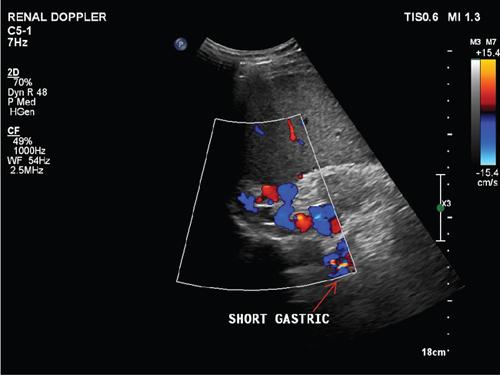

Shrinivas B. Desai, Ritu K. Kashikar, Aman Snehil, Ajay Jhaveri Cirrhosis is a late stage of irreversible scarring of the liver causing abnormality in liver structure and function. Multiple conditions and factors can cause repeated liver damage and scarring ultimately leading to cirrhosis. The most feared complication of liver cirrhosis is the development of hepatocellular carcinoma (HCC). Portal hypertension (PHT) is seen with a variety of conditions but cirrhosis happens to the most important cause. Imaging plays a vital role in noninvasive diagnosis and treatment planning of both cirrhosis and PHT. Liver imaging reporting and data system (LI-RADS) is a standardized reporting system assigning an observation risk of representing HCC. This chapter focuses on discussing aetiologies and imaging of PHT with a lucid review of L1-RADS 2018 version. The portal blood circulation is a unique circulatory circuit as it connects two capillary beds between the liver parenchyma at one end and the gastrointestinal tract and splenic parenchyma at the other end. The portal system ramifies in the liver and ultimately ends in the hepatic sinusoids from where the blood ultimately drains into the inferior vena cava (IVC). The portal vein (PV) originates from the capillary beds in the stomach, intestine and the spleen. The main PV is formed behind the neck of the pancreas by the confluence of the superior mesenteric vein (SMV) and splenic vein. It continues to the porta hepatis where it bifurcates into the left and right branches as it carries nutrient rich but oxygen poor blood to the liver (Fig. 9.9.1). The PV makes up for 75%–80% of the liver’s blood supply while the hepatic artery which arises from the celiac trunk makes up for the remaining 25%. A pathological increase in the portal venous pressure is referred to as PHT. PHT is most often a sequel of chronic parenchymal liver disease and leads to major life-threatening complications due to bleeding from the collateral circulation (most commonly oesophageal varices). Direct measurement of portal pressure (PP) is invasive and often not feasible in most patients and thus imaging plays an important role in the diagnosis of PHT and its complications. The normal portal venous pressure ranges between 5 and 10 mmHg, which is the equivalent of 7–14 cm H2O. The normal hepatic venous pressure gradient (HVPG) is the pressure gradient between the PV and the IVC, is typically 1–5 mmHg. Presence of PHT is indicated by a wedged hepatic venous pressure of more than 5 mmHg. Other definitions include a splenic pressure of more than 15 mmHg or an intraoperative PP of greater than 30 cm H2O. The complications of PHT are seen when HVPG is greater than 10 mmHg and hence this value defines clinically significant PHT. Variceal bleeding is seen with a pressure greater than 12 mmHg. In ideal conditions, the portal circuit is a high flow, low resistance circuit as it has to allow substantial flow rates of 700–1000 mL/min to the hepatic parenchyma from the gastrointestinal tract. Anatomical changes in the organization of the hepatic lobule can result in rise in the portal resistance. These can occur in the form of collagen deposition in the space of Disse, fibrotic scars formed due to regenerative nodule (RN) formation, loss of normal elasticity of the endothelium and distal venous thrombosis. Changes in splanchnic haemodynamics due to factors that increase splanchnic blood flow and increase in intrahepatic vascular resistance due to transformation of stellate cells into myofibroblasts also contribute to the increase in PP gradient. In Western countries, alcoholic cirrhosis and viral cirrhosis are the leading causes of PHT and oesophageal varices. The viral causes form majority of cases leading to cirrhosis and PHT in the Far East and Middle Eastern countries while Schistosomiasis remains an important cause in the African countries. Worldwide, nonalcoholic steatohepatitis (NASH) and hepatitis C are the emerging causes of chronic liver disease (CLD) and PHT. PHT can be classified as cirrhotic and noncirrhotic depending on whether it is associated with cirrhosis or not. This distinction is important as noncirrhotic causes like PV thrombosis are at high risk of development of bleeding but tend to have a better chance of surviving a variceal bleed than a patient with decompensated alcoholic cirrhosis due to preserved hepatic synthetic functions in the former. PHT can also be classified on the basis of the location of the pathology into prehepatic, hepatic and posthepatic causes. Hepatic causes can further be divided into presinusoidal, sinusoidal and postsinusoidal. The causes of portal hypertension have been denoted in Table 9.9.1. The direct measurement of the PP by measuring the HVPG is invasive, expensive not readily available in all patients. Thus, imaging plays an important role in the diagnosis of PHT. Various modalities are used for the imaging diagnosis of PHT. Ultrasonography (USG) and Doppler evaluation have the advantage of being inexpensive, readily available and bedside modality (Table 9.9.2). The role of ultrasound and Doppler in imaging of PHT is to: Grey scale imaging is useful in evaluating the splenoportal anatomy. The evaluation should begin with the liver morphology. Signs of cirrhosis like nodularity of the liver surface with relative atrophy of the right lobe and prominence of the left lobe and caudate should be looked for. Hepatic echotexture appears coarse and more echogenic (Table 9.9.3). Increase in portal venous diameter is a sign of PHT (Fig. 9.9.2). Portal venous diameter of more than 13 or 15 mm has low sensitivity for diagnosing PHT of only 40%–12.5%, respectively. Absolute measurement of the portal diameter as a sign of PHT is also fallacious as in presence of collateral circulation or hepatofugal flow; there may actually be a decrease in the PV diameter. Therefore, a more accurate sign is respiratory variation of PV diameter. An increase in PV diameter of less than 20% with deep inspiration has been reported to indicate PHT with a sensitivity of 80% and specificity of 100%. This has been reported to be an accurate indicator of cirrhosis. Hepatic vein straightness, uniformity of vein wall echogenicity and visualization of at least 1 cm segment of the hepatic vein are the parameters used for evaluation. Splenomegaly is defined as bipolar splenic diameter of greater than 12 cm or largest splenic cross-sectional area passing through the hilum of greater than 45 cm2, and occurs secondary to PHT (Fig. 9.9.3). A total of 65%–80% patients with cirrhosis have splenomegaly on ultrasound. Patients with cirrhosis due to viral hepatitis and primary biliary cirrhosis show splenomegaly more frequently than those with alcoholic cirrhosis. This is an accurate sign of PHT. USG is extremely sensitive with respect to detecting subclinical ascites. Perihepatic space is the most usual site of visualization of minimal ascites. In normal subjects, this ratio is approximately 0.07 and a value above 0.1 suggests the diagnosis of PHT with a 95% sensitivity and specificity. The normal spectral waveform of the hepatic artery is a low resistance flow pattern with forward flow in diastole and a resistivity index in the range of 0.5–0.7. In PHT, the resistivity index of the hepatic artery increases with high resistance flow pattern due to increased peripheral vascular resistance. Resistance index (RI) > 0.78 in the intrahepatic branches of the hepatic artery has been reported to have a sensitivity of 50% and a specificity of 100% for the detection of PHT (Fig. 9.9.11). Pulsatility index (PI) > 1.05 suggests severe PHT with a sensitivity of 86% and specificity of 88% (Fig. 9.9.11). Patency of hepatic veins should be evaluated to rule out Budd–Chiari syndrome as a cause of PHT. The normal hepatic venous waveform (HVW) reflects right atrial activity and this results in a triphasic waveform with one positive and two negative waves. In PHT, this waveform becomes monophasic or biphasic. A monophasic HVW has a sensitivity and specificity of 74% and 95%, respectively, in the diagnosis of severe PHT (Fig. 9.9.12). Dilatation of the splanchnic veins – the SMV and the splenic vein – more than 11 mm are suggestive of PHT with a sensitivity and specificity of 72% and 100%, respectively. A reduction in the respiratory variation of the splenic vein and SMV to less than 40% had a sensitivity and specificity of 79.7% and 100%, respectively, for the diagnosis of PHT (Fig. 9.9.13). The splenic artery reveals an increase in the resistivity index and an RI of >0.63 and a PI of >1 have a sensitivity and specificity of 84.6% and 70.4% for the diagnosis of PHT. Presence of portosystemic collaterals like patent paraumbilical vein, dilated left gastric and short gastric veins are 100% specific sign for PHT (Figs. 9.9.14–9.9.16). Recanalization of the paraumbilical vein, known as the Cruveilhier–Baumgarten syndrome is observed in 43% of patients with PHT, and this is the easiest collateral to assess during the US examination. Various portosystemic collaterals that occur in PHT have been discussed in details in subsection on CT findings in PHT. No Doppler parameter is considered reliable enough to measure PP with sufficient accuracy for use in clinical practice. Oesophageal varices are often present in patients with portosystemic collaterals. Appearance or increase in number of collaterals along with splenomegaly has a high association with variceal formation and growth. USG helps in diagnosis of prehepatic causes like portal stenosis or thrombosis by demonstrating the patency and morphology of the splenoportal system. Arteriovenous fistulae and tumours causing vascular thrombosis as aetiology can be readily detected. USG helps in diagnosis of features of cirrhosis and thus helps differentiate noncirrhotic causes of PHT. USG allows diagnosis of fatty liver disease, which is an emerging cause of cirrhosis. Among the posthepatic causes, USG aids in establishing the diagnosis of Budd–Chiari syndrome by demonstrating the patency and morphology of the IVC and hepatic veins. Owing to the inability of CT to detect flow direction, portal flow rates or pressure gradients, CT is not the primary modality in diagnosis of PHT. Similar to USG dilatation of portosystemic system is a feature of PHT (Fig. 9.9.17). Changes in cirrhosis if present can be seen in the form of surface nodularity, nodules and fibrous septae. CT plays an important role in diagnosis of portal venous thrombosis and evaluating its extent. An acute thrombus is seen as a hypodense filling defect in the vessel causing distension of the venous lumen. Surrounding fat stranding can be seen. A chronic thrombus appears as an eccentric filling defect usually along the wall and is often associated with decrease in vessel diameter. Calcification may be seen in chronic thrombi. Multidetector computed tomography (MDCT) is a useful tool to evaluate portosystemic collateral circulation and recognize complications of PHT. 3D angiography can help understand portal venous and complex variceal anatomy and plan treatment. The various portosystemic collaterals are discussed below. They can be classified into those draining into superior vena cava (SVC) and those draining into the IVC. Magnetic resonance imaging (MRI) is a noninvasive modality used in the evaluation of PHT without the use of ionising radiation. It provides evaluation of parenchymal abnormalities, collaterals and characterization of tumours (Fig. 9.9.28). Spin echo sequences allow characterization of liver masses and liver parenchyma. Loss of flow void allows for detection of thrombosis. Time-of-flight (TOF) angiography is useful in assessing the portal venous system and allows for successful detection of PV thrombosis. The disadvantages of TOF are motion artefacts caused by breathing, long acquisition times and incomplete coverage of the portal venous system. Novel imaging techniques include phase contrast, T1 mapping and magnetic resonance elastography (MRE). The advantage of phase contrast over TOF imaging is that phase contrast imaging acquires information regarding the flow direction in addition to the information regarding the flow velocity. On-phase contrast images signal within vessel is hyperintense when flow is cranial and hypointense when flow is caudal. Look-Locker imaging technique using gradient echo (GRE) MRI sequences with inversion recovery pulse is used to quantify fibrosis by measuring precontrast T1 relaxation times. Interventions in PHT can be aimed at diagnosis or more commonly at management of complications of PHT. HVPG measurement, which is the gold standard for the diagnosis of PHT, can be achieved through cannulation of the PV. Transjugular hepatic biopsy is another diagnostic invasive technique that also allows indirect measurement of PP. Disadvantages include deterioration of hepatic function caused by diversion of portal venous blood flow and shunt dysfunction. TIPSS is contraindicated in patients with congestive heart failure, severe pulmonary hypertension, severe tricuspid regurgitation and hepatic failure. In this technique, a catheter is advanced from the femoral vein into the outlet of the gastrorenal, usually in the region of the left renal vein. The shunt is then occluded with a balloon and sclerosant is injected retrograde to occlude the gastric varices. Histological development of RNs surrounded by fibrous septae in response to chronic liver injury, progressing PHT and end-stage liver disease is termed as cirrhosis. Although initially considered an end-stage phenomenon in CLD, recent evidence suggests that the histological fibrosis can be reversible in early stages with the initiation of specific therapies, for example, in viral cirrhosis with the initiation of antiviral therapy. The one-year mortality rate in cirrhosis varies widely from 1% to 57% depending on the occurrence of complications. Cirrhosis can have a wide variety of causes ranging from congenital to acquired and infectious to noninfectious. It is also a major aetiologic risk factor for the development of HCC. Imaging plays an important role in aetiologic diagnosis of this diverse entity as well as in the diagnosis and management of its complication and surveillance for oncological transformation.

F. Portosystemic collateral channels (Table 9.9.5)